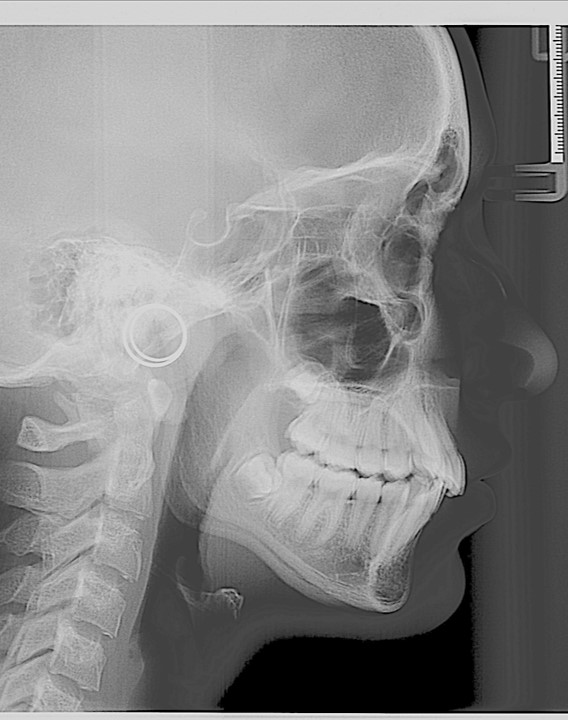

Chief complaint: We present the case of a 12-year-old female patient who came for an orthodontic evaluation, motivated by a family history of treatment. Clinical and radiographic analysis revealed a skeletal Class II malocclusion with molar and canine relationships also in Class II, moderate crowding in both arches, a deviation of the dental midline, and ectopic eruption of tooth 13. No functional issues with breathing or swallowing were observed, and oral health was generally good. A slight mandibular retrusion was noted in the soft tissue profile. A treatment plan was proposed using the Angel Aligner Pro system, aiming to correct dental misalignments and improve facial harmony through a minimally invasive, growth-adapted approach.

Clinical examination and diagnosis

- Woman ; 12/3 years

- Skeletal Class II

- Molar and canine Class II

- Upper and lower dentoalveolar compression

- Increased overjet and overbite

- Upper midline deviated 0,5 mm to the right

- Moderate upper and lower crowding